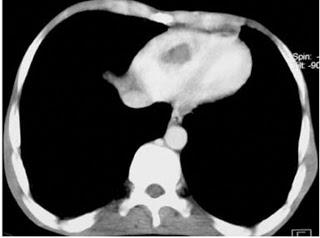

Angioscanner thoracique montrant une thrombose intra ventriculaire droite. In Revue des Maladies Respiratoires Volume 25, Issue 1, january 2008, Pages 69 - 72